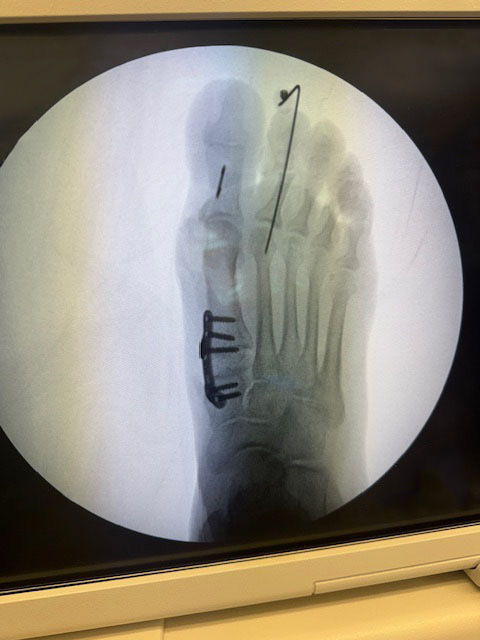

In regards to my total ankle replacement surgery by Dr Stoddard. In October 2025 after I was placed in my room in the hospital I experienced no PAIN at all. At first thought as part of the surgery I had a implant pain medication pump. No I did not and experienced no subsequent pain needing medication after that at all. I took care to elevate the ankle as requested subsequently. This was surprising considering the nature of the surgery and the parts implanted. I am still recovering but the pain has been very little. Physical Therapy has been a blessing to help me gain normal walking function and I recommend it highly to all patients.

This testimonial is regarding Dr. Sean Stoddard and the work he performed on my ankle in July of 2012. Prior to being referred to Dr. Stoddard, I was in constant pain as the result of an ankle injury that had occurred during a motorcycle accident in 1993. Visits to orthopedic surgeons had resulted only in recommedations for an ankle fusion, a procedure that I was told by former recipients may not be successful at stopping the pain. The pain in my ankle had become unbearable during the last couple years leading up to my first consultation with Dr Stoddard. I was walking with a cane and taking pain medication, which was affecting my quality of life. A third party mentioned Dr Stoddard and his Foot and Ankle Clinic. My consultation with him revealed that I was a candidate for a total ankle or Inbone® ankle replacement. The promise of pain relief without a fusion seemed almost too good to be true. Surgery was scheduled and performed. After several months of rehab I was walking and without pain. Today my quality of life has vastly improved and I will always be grateful to Dr. Stoddard.

In March 2011 I contracted Necrotizing Fasciitis in my lower left leg/ankle/foot. The infection resulted in the loss of nearly 40% of my ankle bone and limited my range of movement to less than 10% – up/down, no lateral movement what so ever. Also my foot and ankle were in constant pain. I was on a daily regimen of 75mg Tramadol 2x’s daily until the ankle was replaced in January 2014 by Dr. Stoddard.

Dr. Stoddard evaluated my ankle, my desire to increase mobility and reduce the chronic pain. After several consults with other Orthopedics to discuss my ankle and its ‘current’ condition – Frozen bone mass, Dr. Stoddard recommended a total ankle replacement.